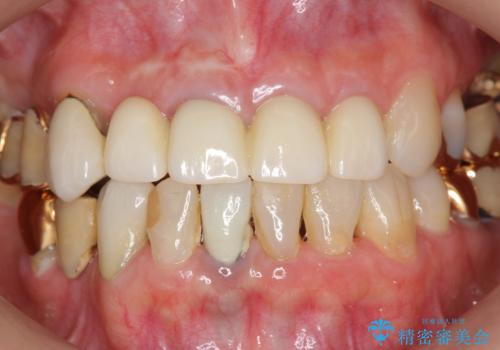

即切歯の抜歯を行う場合犬歯を含めたブリッジによる補綴計画を立てることが多いですが、今回は犬歯から大臼歯にかかる大きなブリッジが既に装着されていたため予算とご希望を相談し前歯のみの延長ブリッジ補綴で治療を行っていくこととしました。

- 54万円(仮歯・感染根管治療・ファイバーコア・ジルコニアクラウン×4) (税別)費用は治療当時の料金となります

歯列全体を治療の対象とする治療計画が予算や期間により難しい場合、状況に応じて最善の治療結果が出せるよう治療のゴールを相談しながら決定することが可能です。